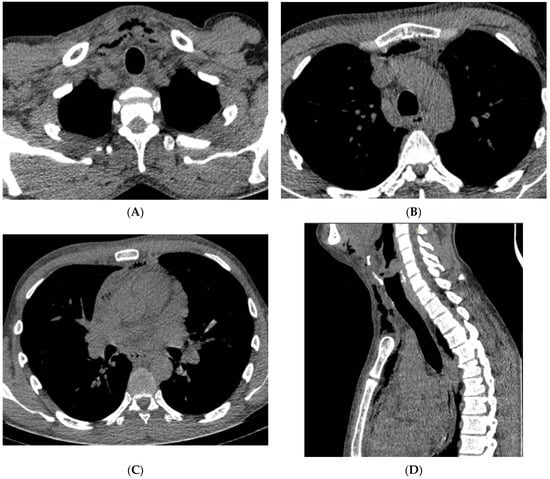

| Neck CT | Pus collection - in the left submandibular area - around the hyoid bone - around the left piriform recessus - around the thyroid cartilage - around the sternocleidomastoid muscle | Presence of a gas collection with delamination of the soft tissues of the neck in the area of the parapharyngeal space on the left Gas collections in - both palatine tonsils - anterior cervical space - left carotid space up to the level of the aortic arch - bilateral submandibular and sublingual space | Multiple air collections that stratify the tissues of the neck on the right side | Multiple air collections that stratify the superficial and deep tissues of the neck and enter the mediastinum |

| Chest CT | pus collection: ventral from the thyroid gland measuring 68/14 mm, with a density of 34–40 HU reaching the carina | Purulent collection starting from the neck and reaching the anterior mediastinum above the carina, presence of gas collections | Multiple air collections involving all departments of the anterior mediastinum above the carina | Massive pneumomediastinum, presence of fluid-purulent collections in the anterior and posterior lower mediastinum below the carina |